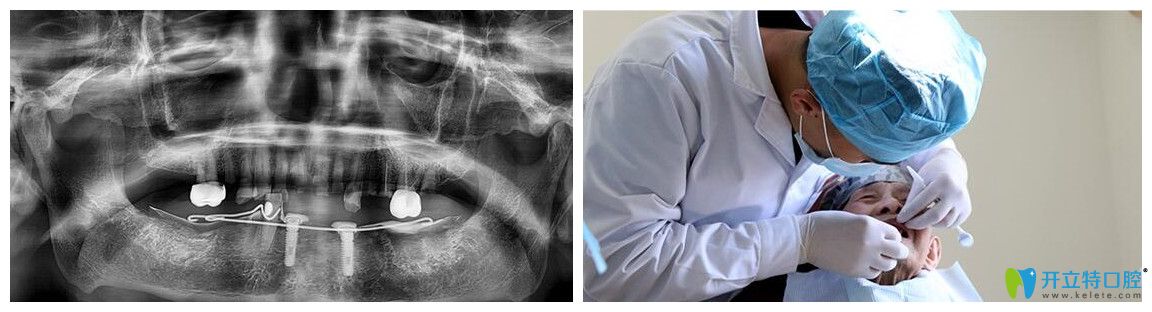

侯主任為韓老實施精準(zhǔn)種植手術(shù)圖

術(shù)前,醫(yī)護(hù)人員為韓老又進(jìn)行了一遍CT口腔檢查。侯國鎮(zhèn)主任用“高齡精準(zhǔn)種”技術(shù)為韓老實施精準(zhǔn)種植手術(shù)。但在韓老進(jìn)到手術(shù)室的時候,主任察覺到了韓老的緊張感,悄悄鼓勵他:“放輕松,相信我,治療過程很快的,而且也不會有太大的疼痛?!痹谥魅蔚囊龑?dǎo)下,韓老狀態(tài)很放松,手術(shù)也很順利的完成了。?

韓老拍CT和醫(yī)生檢查的圖片

術(shù)后CT片顯示,韓老口內(nèi)的種植體植入非常周正、位置和導(dǎo)板設(shè)計完全吻合,手術(shù)非常成功。王明霞醫(yī)生正在給韓老佩戴牙冠修復(fù)體。